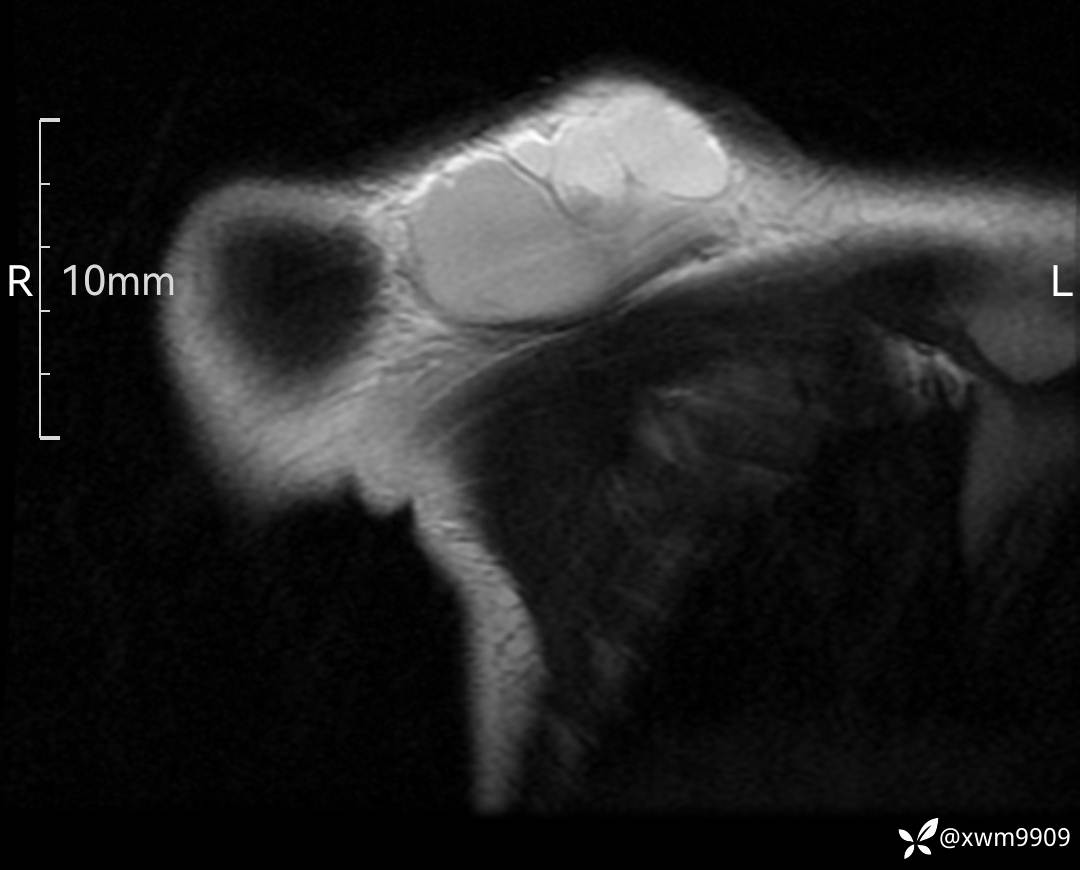

3、查体,右锁下方可及一约5x6Cm肿物,软丶边清丶未见明显发红,肤温不高,压痛明显,不可推动,稍有波动感。其他无特殊。

CT:

2、CT、MR肿块内可见液-液平面,常见有哪些疾病。